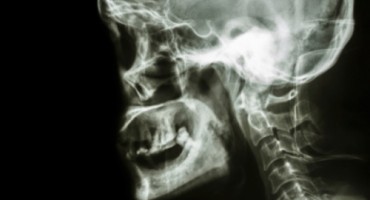

Zbog stalnog krvarenja iz nosa, mladi se Saudijac obratio liječniku. Nalazi rendgenskih snimki otkrili su da mu u nosu raste zub dug oko 1,3 centimetra, objavio je časopis American Journal of Case…